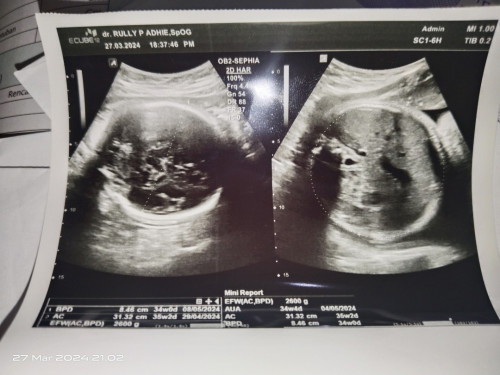

Bunda2 ada yg bisa baca hasil usg kh,soalya saya bingung apakah 34 minggu atau 35 minggu usia nya ?

Ini gambar usg nya pas tgl 27 maret kmaren

usia kandungannya ttp pake yg udh ada selama ini bun, yg dr hasil tm1 atau dr hpht. kl yg di hasil usg skrg mah ukuran janinnya skrg, bpdnya 34w, acnya 35w, dst. emg begitu, jd gausah liat usia kandungan dr hasil usg pas udh hamil tua gini. paling sih aku suka liat EFW(bbj) buat rata2 hasil pengukuran yg skrg. krn efw itu dptnya dr gabungan ukuran kepala badan dan kaki. tp disitu aku ga liat GA nya EFW, cuma ada hasilnya aja brp gram, ga ada weeksnya